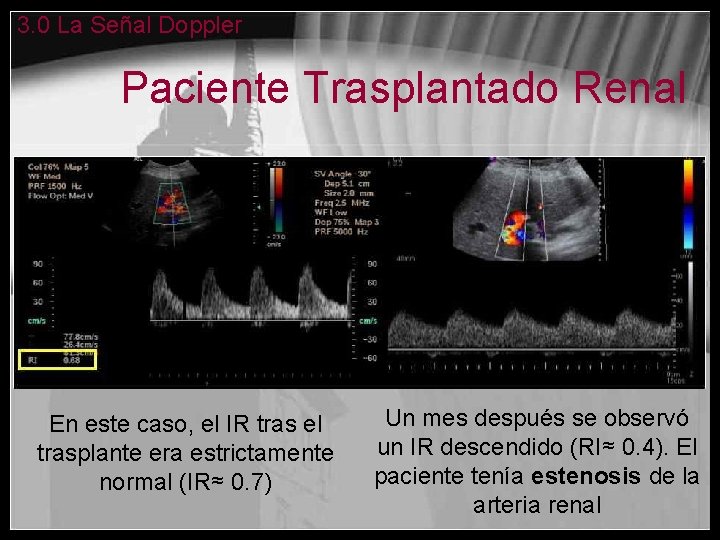

3. 0 La Señal Doppler Paciente Trasplantado Renal En este caso, el IR tras el trasplante era estrictamente normal (IR≈ 0. 7) Un mes después se observó un IR descendido (RI≈ 0. 4). El paciente tenía estenosis de la arteria renal